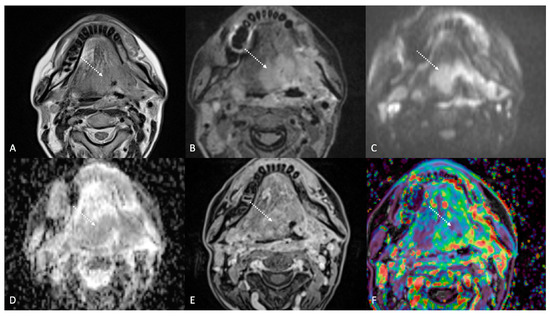

Figure 4.

Post-treatment magnetic resonance imaging (MRI) of a 36-year-old female patient affected by nasopharyngeal carcinoma with left lymph node metastasis (T3N3) and tumoral extension to bilateral Ronsemüller fossa, left nasal choana, and middle skull base, recently treated (3 months before) with chemoradiotherapy (CRT). Early post-treatment MRI demonstrated post-CRT inflammatory residual tissue (white striped arrows) in the left Ronsemüller fossa and ipsilateral nasal choana. Post-CRT inflammatory changes showed hyperintense signal on T2-weighted (A), T2-weighted fat-saturated (B), and diffusion-weighted b800 images (C); high apparent diffusion coefficient value (1.53 × 10−3 mm2/s) (D). After gadolinium contrast agent injection, post-CRT inflammatory residual tissue shows submucosal enhancement of 5 mm thickness (E), and very high K(trans) value (595.25 × 10−3 mm2/s) on dynamic contrast enhancement-perfusion weighted imaging (F). Ratio between K(trans) values of the primitive tumor and residual tissue after CRT, standardized with respect to K(trans) value of the ipsilateral trapezius (K(trans)post/pre/muscle), was 3.17. These findings suggested an increase in capillary permeability caused by CRT.